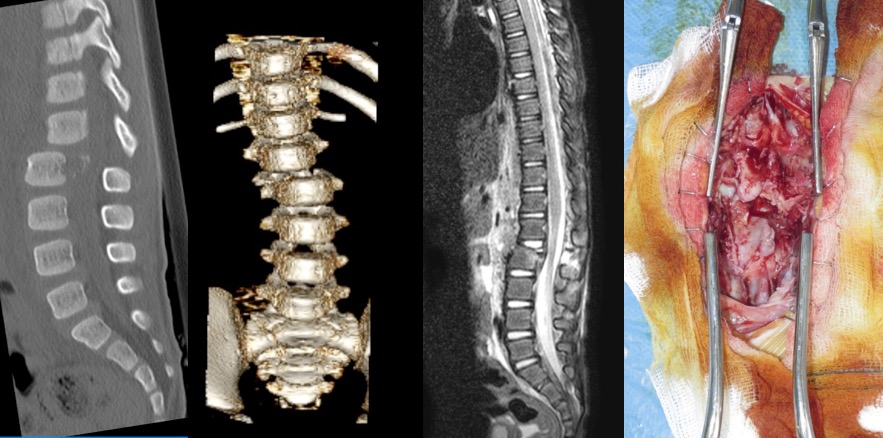

- le tassement marginal antérieur (Cf. ci-contre) est souvent asymptomatique, découvert sur le bilan radiologique standard ; il est sans conséquences mais atteste de la violence du secouement ; dans ce contexte il faut s’assurer du statut nutritionnel car une carence en vitamine D, liée à un contexte de négligence, prédispose à ce type de fracture.

- la fracture-dislocation rachidienne est rare, attestant d’un

traumatisme particulièrement brutal. il s’agit d’une lésion instable car il existe une rupture de tous les éléments ligamentaires et une avulsion du plateau discal ; cette lésion est donc menaçante au plan neurologique.